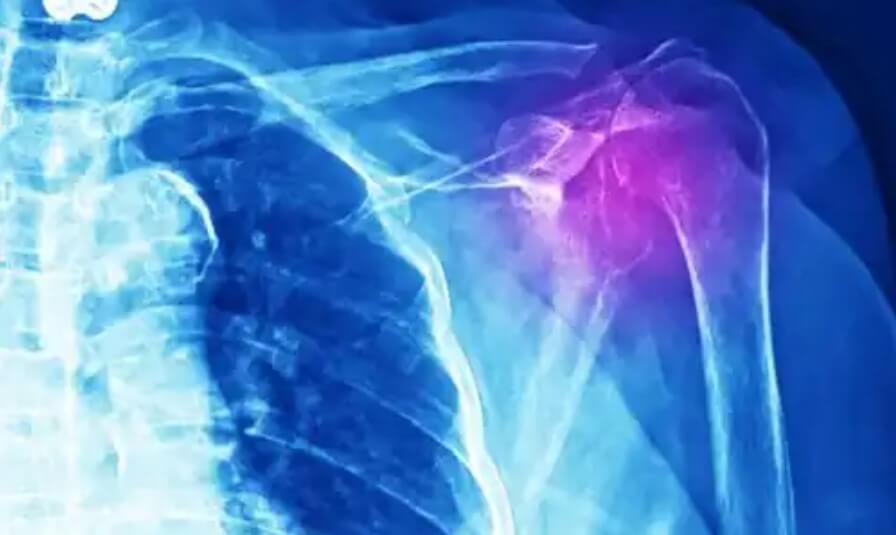

Οι γιατροί πρέπει να κάνουν διάφορες εξετάσεις για τη διάγνωση αυτού του είδους τραυματισμού. Θα μπορούσε να είναι ακτινογραφία, υπερηχογράφημα, μαγνητική τομογραφία ή αξονική τομογραφία. Επιπλέον, πρέπει να κάνουν ιατρική εξέταση και λεπτομερή μελέτη του ιατρικού ιστορικού του ασθενούς.